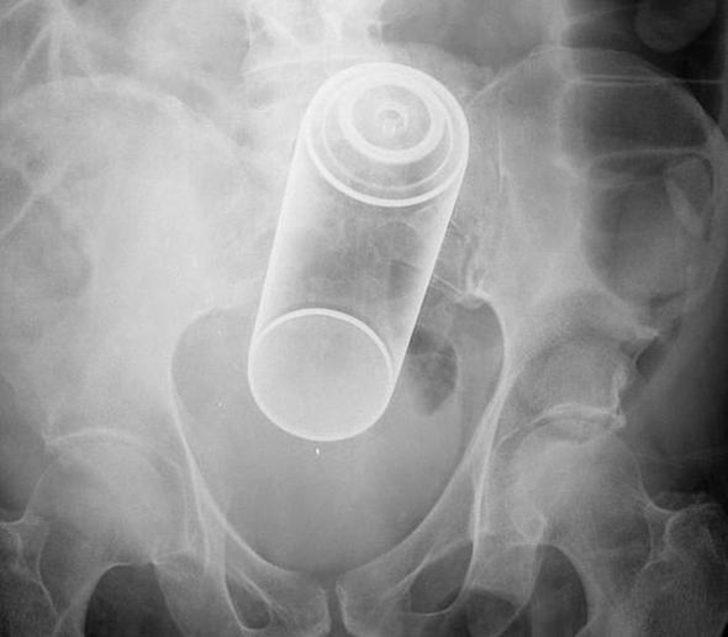

Açıklanan raporlar arasında acil durum şikayetiyle ilgili olan görenleri hayrete düşürdü. Oldukça ilginç bulunan bu raporda röntgen cihazlarda çekilen filmler yer aldı. Bakın o filmlerde nasıl görüntüler vardı?

Röntgen filmlerinden öyle şeyler çıktı ki...